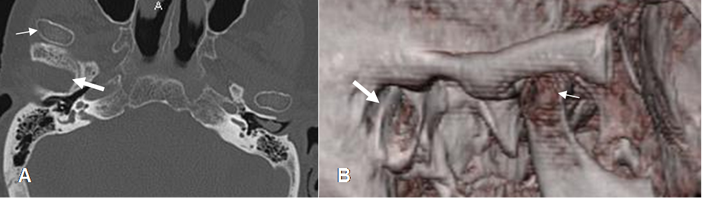

Fig 20. Trauma.

A: TAC axial y B: TAC reconstrucción en 3D. Luxación del cóndilo mandibular derecho (Flecha delgada), el cual se localiza por delante de la cavidad articular. (Flecha gruesa).